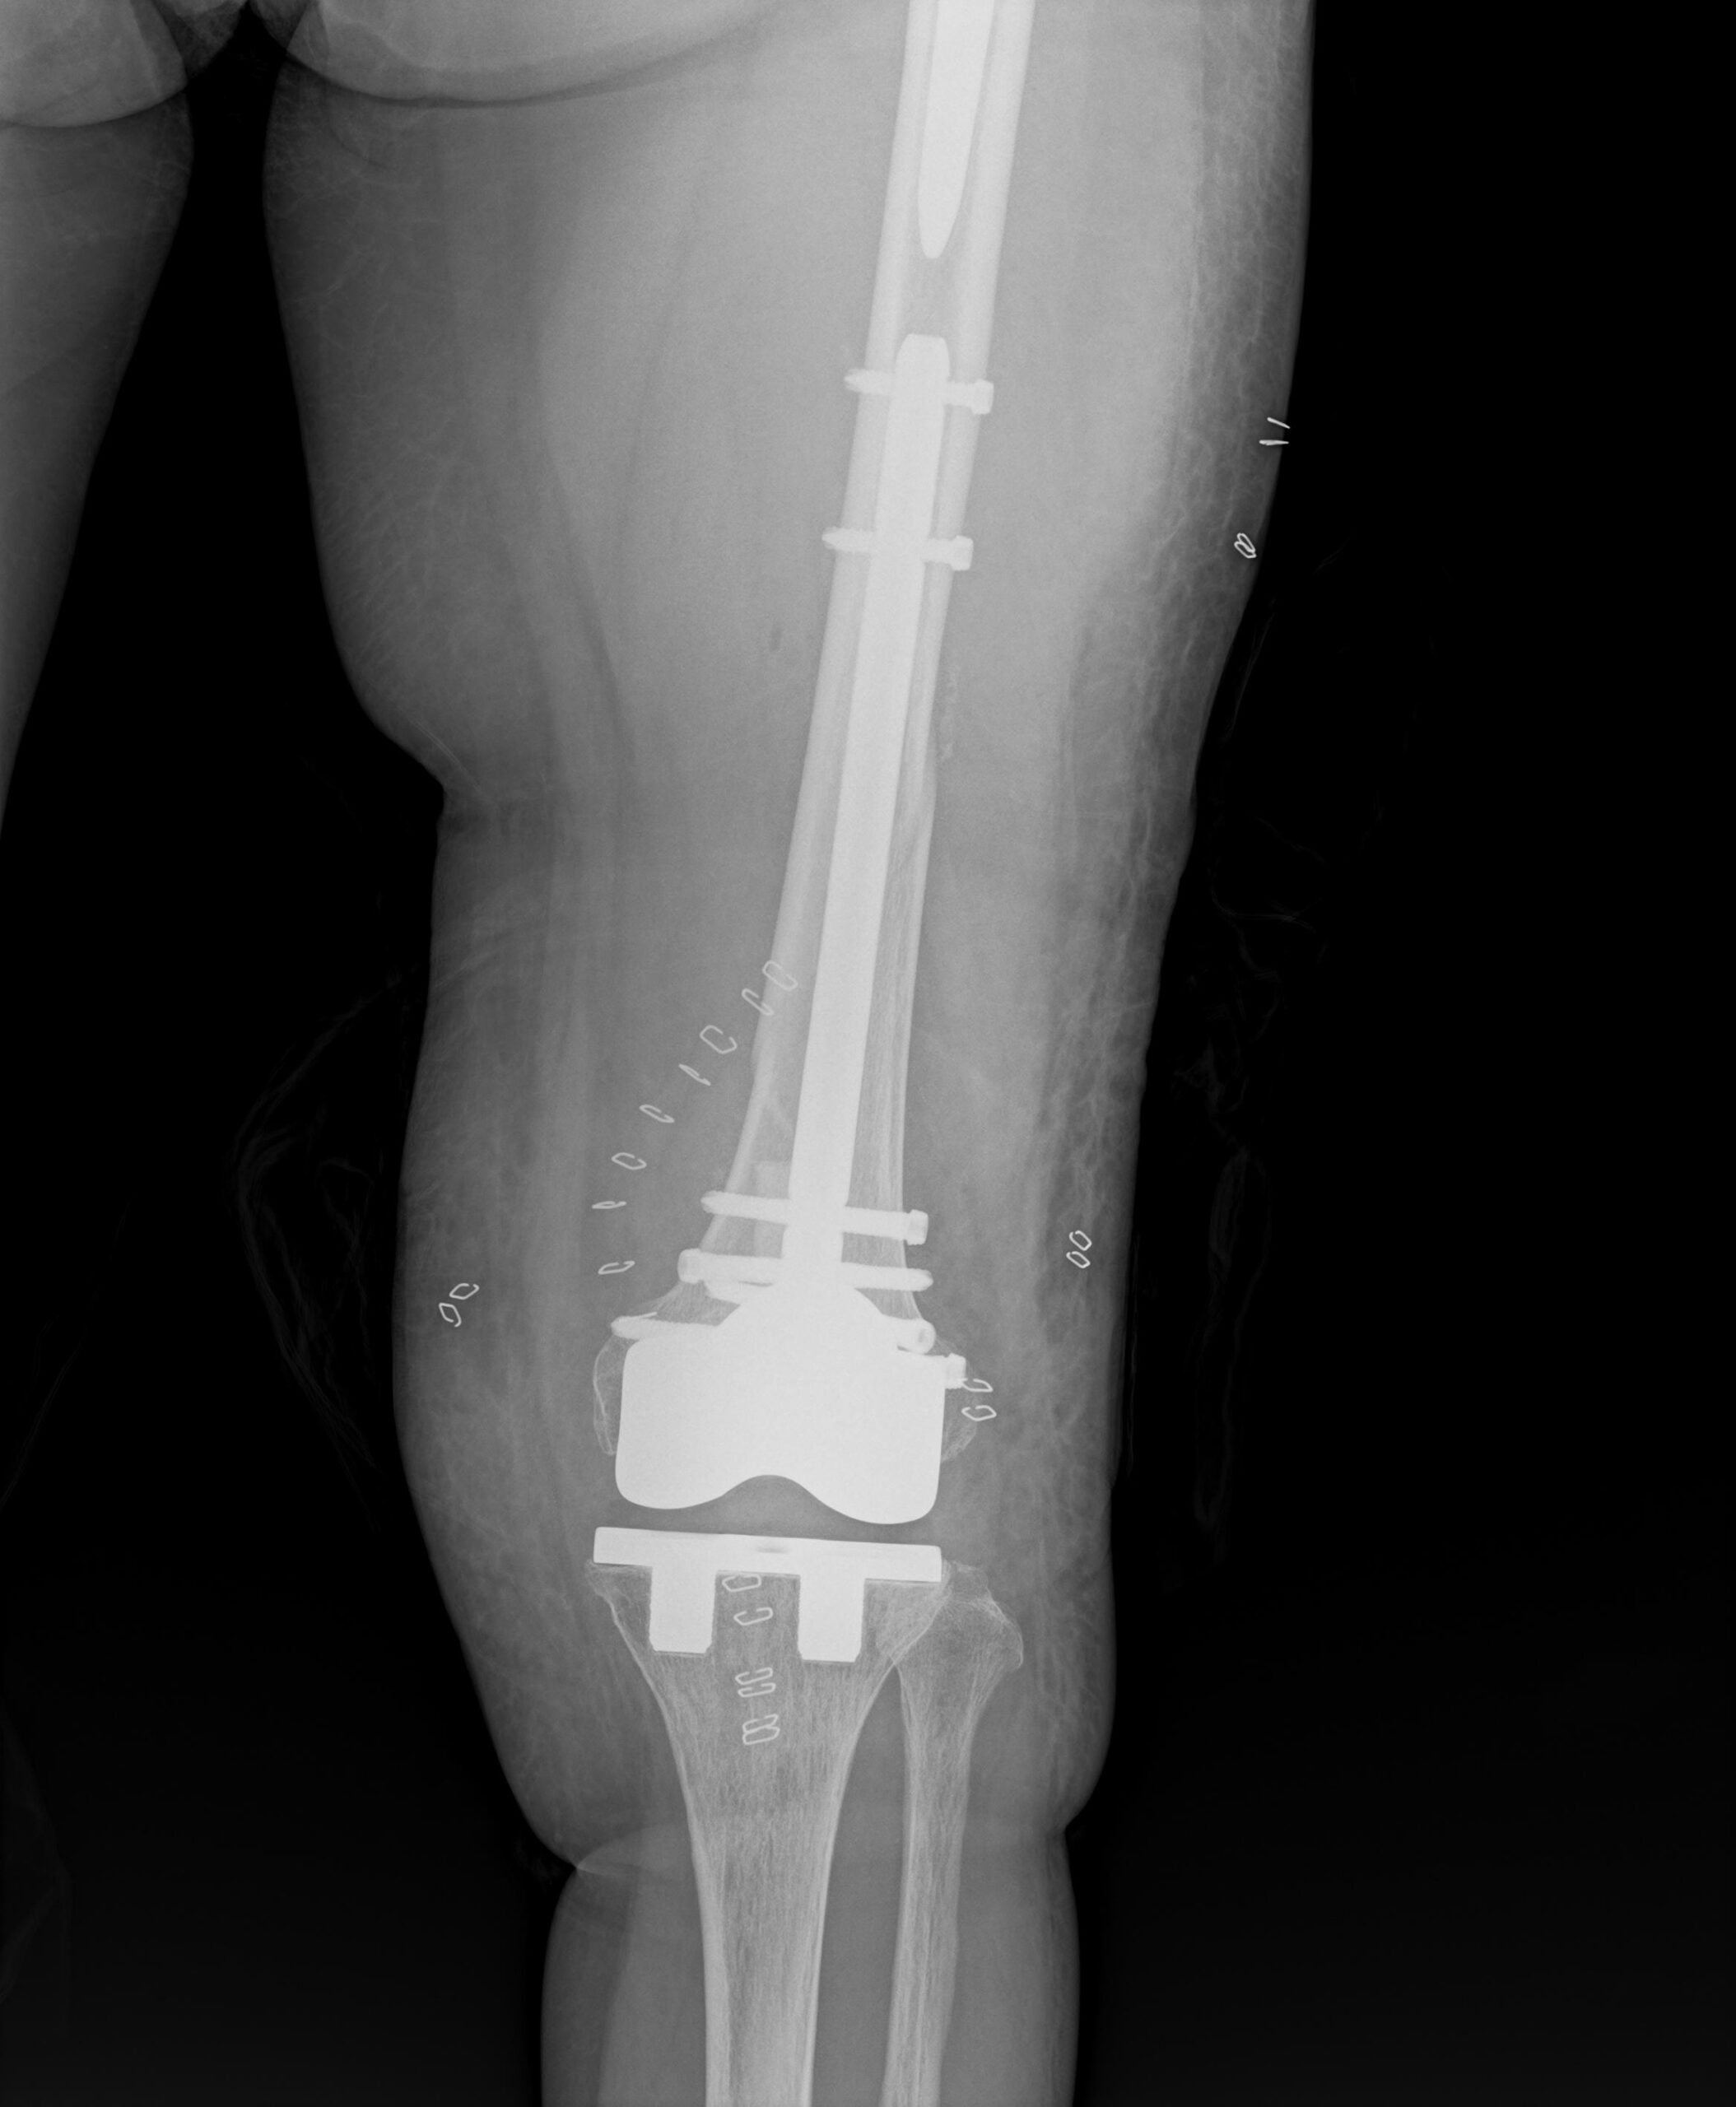

通常であれば、膝関節を開けて逆行性髄内釘挿入手術を行います。

本来はそれほど難易度が高い手術ではありませんが、刺入部に膝人工関節、

固定すべき大腿骨近位に人工股関節があるため、挿入方向や髄内釘のサイズが限られ、

骨折整復が困難となります。

強固な固定が得られたので、激痛のため身じろぎもできなかった状態から、

手術翌日には車椅子に移乗できるようになりました。

CPM(膝可動域訓練機械)を早期に開始し、関節拘縮を予防します。

X線検査で骨癒合の程度をみながら、徐々に体重をかけていき

2〜3ヶ月での退院を見込みます。